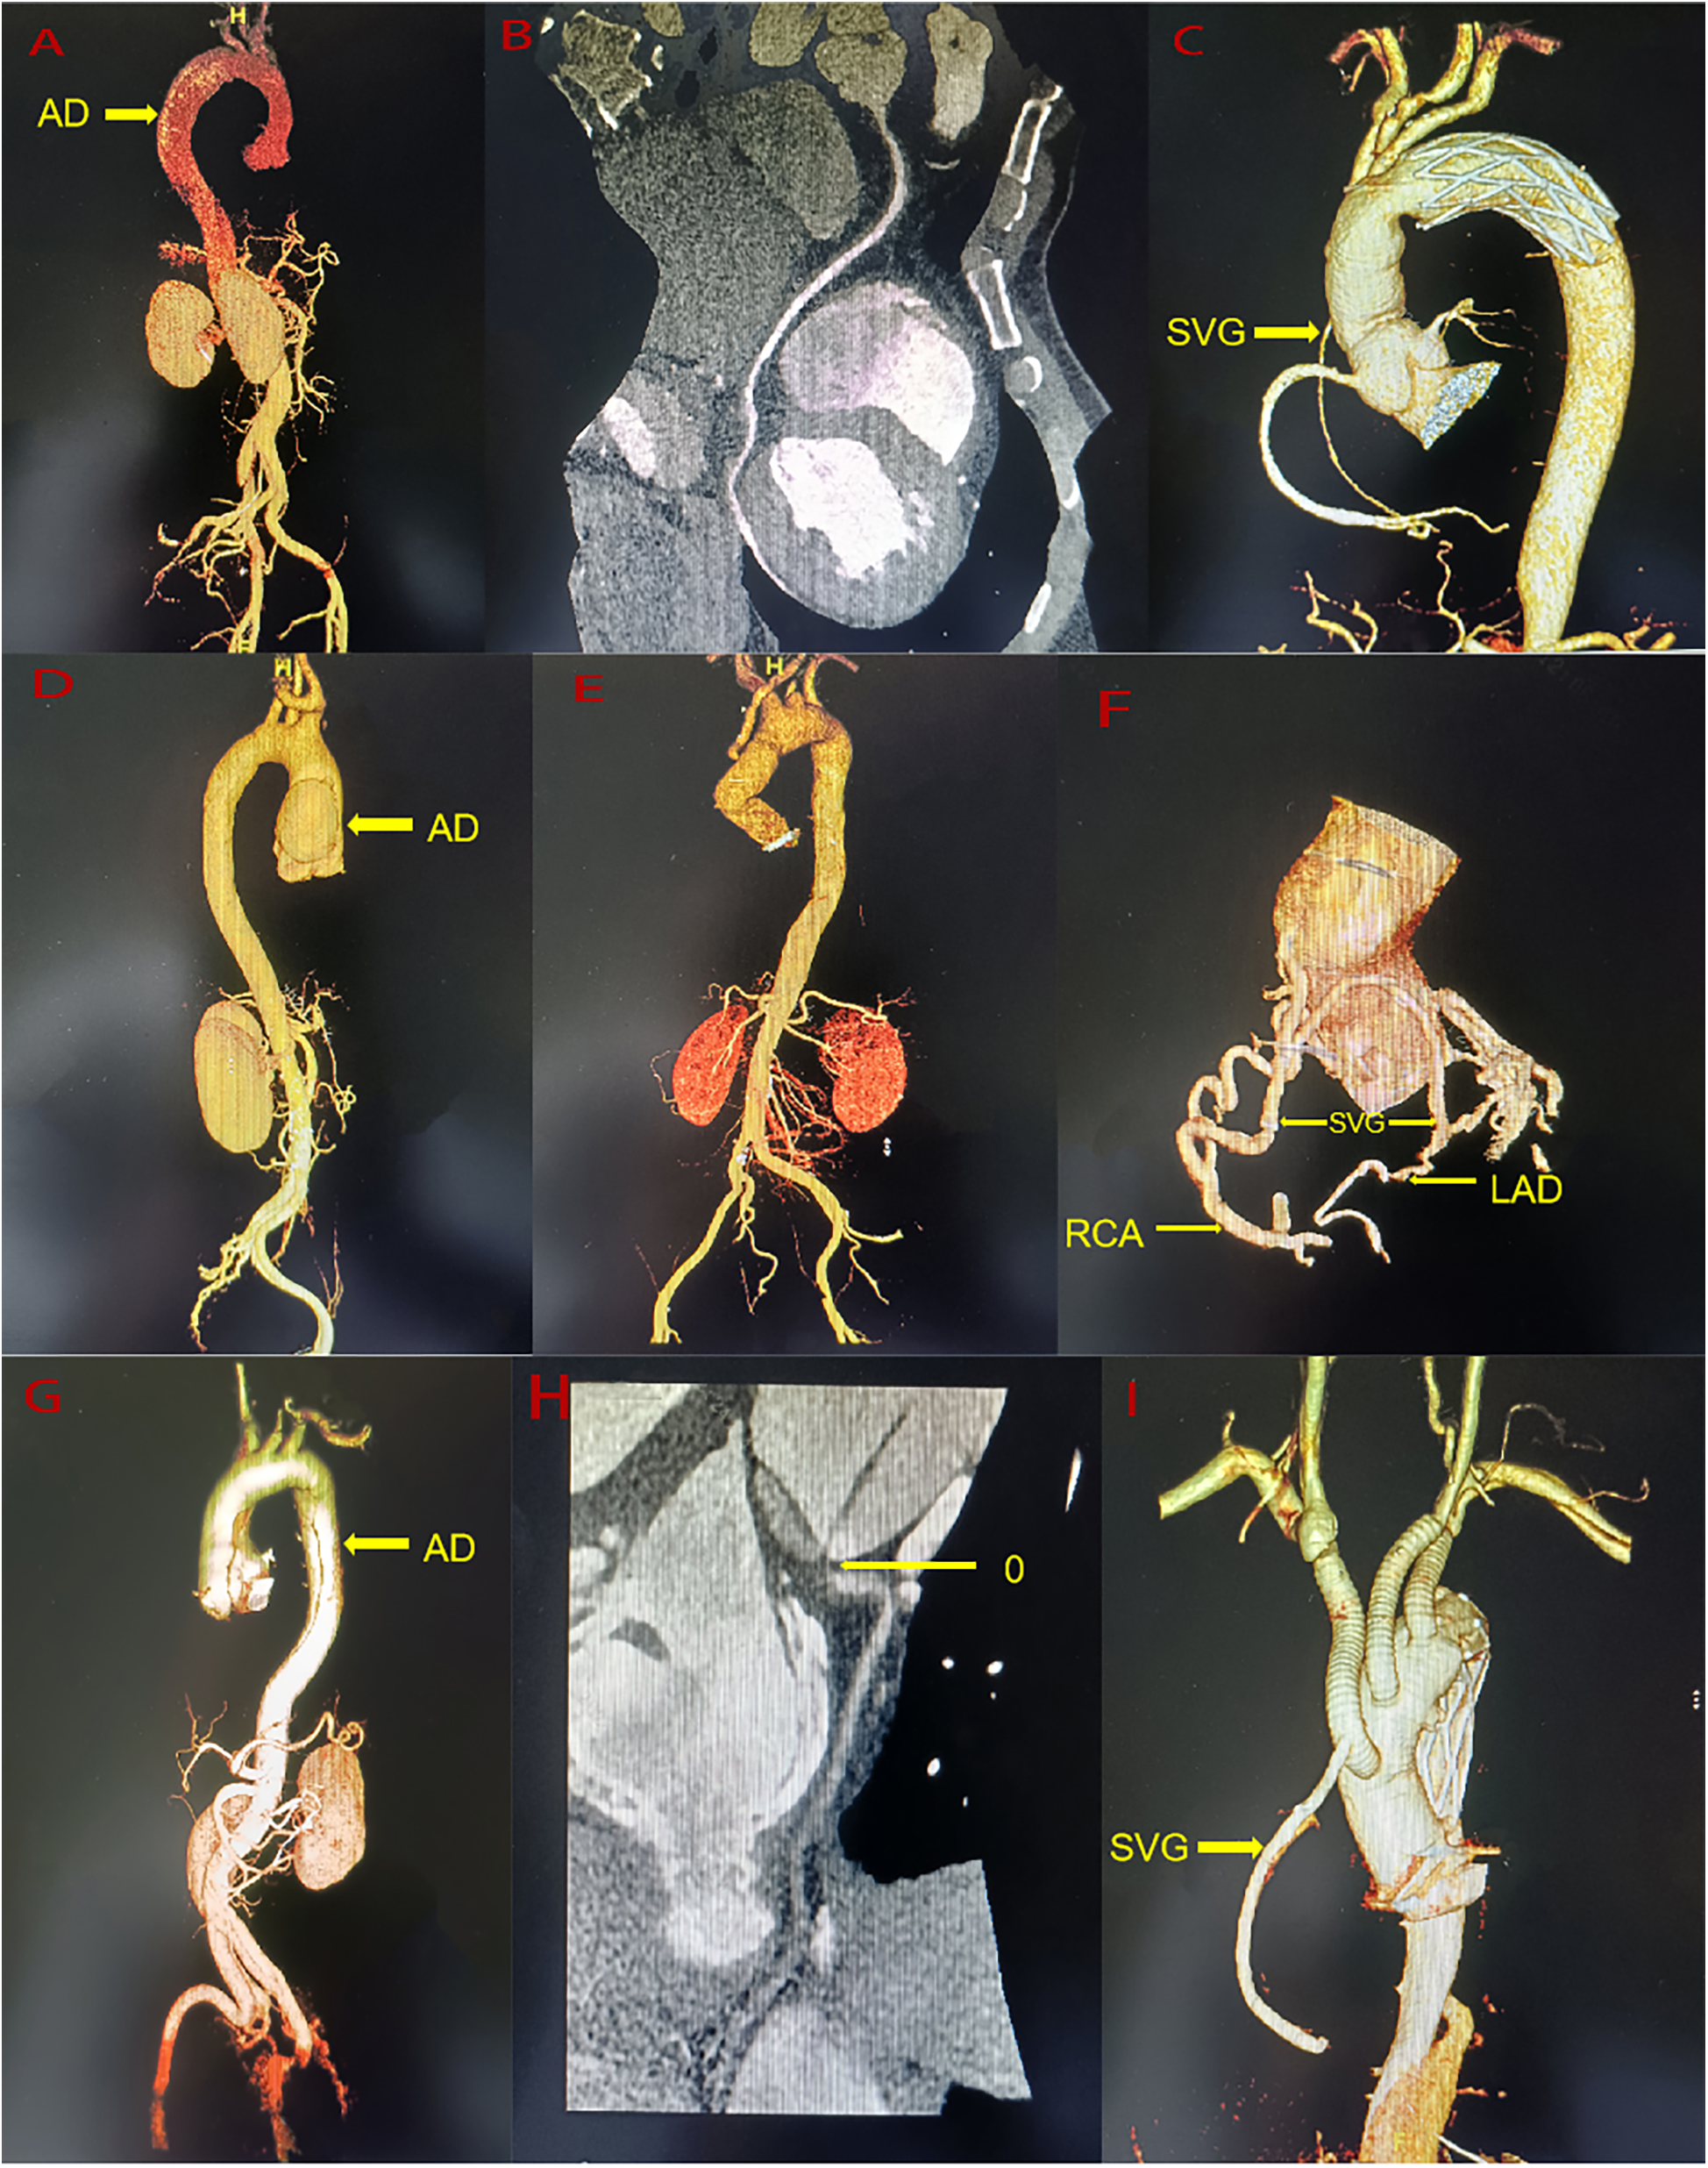

A 44-year-old man (height 168 cm, weight 88.5 kg) was admitted to the emergency department of our hospital with chest pain persisting for 8 h. He had a history of hypertension but did not take medication regularly. His vital signs upon admission included a right arm blood pressure of 138/77 mmHg, a pulse of 70 beats/min, a respiratory rate of 18 breaths/min, and an oxygen saturation (SpO2) of 97%. A 12-lead electrocardiogram revealed ST-segment depression in the II, III, and aVF leads. Myocardial enzyme levels were significantly elevated, including CK-MB at 182 ng/ml (0–6 ng/ml) and troponin at 24.54 ng/ml (0–0.08 ng/ml). A pre-operative computed tomography angiogram (CTA) of the entire aorta, coronary artery and supra-aortic vessels revealed ATAAD with a rupture located in the ascending aorta (Figure 1A–B). The dissection flap extended from the ascending aorta to bilateral common iliac artery, right external iliac artery and left internal iliac artery. Celiac trunk artery, superior mesenteric artery, bilateral renal artery and most of intercostal arteries originate from the true lumen, while the inferior mesenteric artery originate from the false lumen. Eccentric thickening of the wall of the proximal segment of the right coronary artery and the proximal segment of the left ventricular posterior branch was observed. A small aneurysm was noted in the M2 segment of the left middle cerebral artery, and the lumen of the right anterior cerebral artery appeared slender. Pre-operative echocardiography revealed coordinated movement of the left and right ventricles with normal contraction amplitude and a left ventricular ejection fraction (LVEF) of 59%. Emergency physicians diagnosed ATAAD with AMI, and emergency surgery was planned in collaboration with the cardiovascular surgery team. For the surgery performed via median sternotomy, cardiopulmonary bypass (CPB) was established through the axillary artery, femoral artery, and right atrium. The ascending aorta was clamped proximal to the brachiocephalic artery and opened to inspect the coronary ostial lesions. A cold blood cardioplegic solution was perfused through the coronary ostium, and no intimal tear was found. The heart was covered with ice. The dissected aorta was resected, intima and media of the aorta were resected, the false lumen blood clots were cleared, and a large epicardial hematoma on the right ventricular surface was explored. Sequential coronary artery bypass grafting (CABG) was performed using a saphenous vein graft from the left ventricular posterior branch (PL) to the posterior descending branch (PDA). Proximal aortic reconstruction was performed using the adventitial inversion technique. Circulatory arrest was initiated at a bladder temperature of 28℃ with bilateral-anterograde cerebral perfusion. A 30-mm self-expandable elephant trunk stent graft was inserted into the true lumen of the descending aorta, and aortic arch reconstruction was performed using a 30-mm four-branched arch graft. When the heart resumed beating and body temperature normalized, intraoperative transesophageal echocardiography revealed decreased left heart function with an LVEF of 32%, the patients have evidence of cardiogenic shock (systemic systolic pressure <90, urine output <30 ml/hour, lactate >2), necessitating the initiation of ECMO through the axillary artery and femoral vein (rotation speed: 2,500 R/min, flow rate: 3.360 L/min). The right coronary saphenous vein graft flow was 58 ml/min, and the pulsatility index was 2.0 by transit time flow measurement (TTFM). The CPB duration was 337 min, aortic cross-clamping time was 153 min, and the circulatory arrest time was 19 min. ECMO was discontinued on post-operative day 3, and the patient was extubated on day 7. The patient spent 18 days in intensive care and 24 days in the hospital. Echocardiography at discharge revealed hypokinesis of the middle and the lower segments of the right ventricle and lower posterior wall of the left ventricle, with an LVEF of 55%. Ultrasound at discharge revealed venous thrombosis in the bilateral lower limbs and right upper limbs. The CTA revealed bilateral scattered pulmonary embolism with an unobstructed artificial vessel and a well-dilated elephant trunk stent without internal leakage. The false lumens distal to the stent had thrombosed. At 2 years and 6 months of follow-up, the patient exhibited normal heart function and could perform normal daily activities. Recent echocardiography revealed normal left and right ventricular wall movements, with an LVEF of 63%. Recent CTA revealed an unobstructed great saphenous vein graft, occlusion of the left ventricular posterior branch, unobstructed artificial vessels, a well-attached elephant trunk stent to the aortic wall, thrombosis and occlusion of the false lumen (Figure 1C).

Figure 1

(A) A pre-operative the entire aorta CTA of case 1. (B) A pre-operative the right coronary artery CTA of Case 1. (C) A post-operative the entire aorta CTA of Case 1. (D) A pre-operative the entire aorta CTA of Case 2. (E) A post-operative the entire aorta CTA of Case 2. (F) A post-operative the coronary artery CTA of Case 2. (G) A pre-operative the entire aorta CTA of Case 3. (H) A pre-operative the right coronary artery CTA of Case 3. (I) A post-operative the entire aorta CTA of Case 3. AD, aortic dissection; RAC, right coronary artery; LAD, anterior descending branch; SVG, saphenous vein graft.

A 41-year-old man (height 170 cm, weight 49 kg) was admitted to the emergency department of our hospital with persistent chest pain for 2 days. He had no prior medical history. His vital signs upon admission included a right arm blood pressure of 122/75 mmHg, a pulse of 99 beats/min, a respiratory rate of 17 breaths/min, and a SpO2 of 97%. A 12-lead electrocardiogram revealed ST-segment depression in leads V4-V6. Laboratory tests showed elevated troponin at 2.54 ng/ml (0–0.08 ng/ml) and CK-MB at 6.76 ng/ml (0–6 ng/ml). Pre-operative CTA of the entire aorta, coronary artery and supra-aortic vessels revealed ATAAD, with the entry located in the ascending aorta (Figure 1D). The dissection was limited from the aortic sinus to ascending aorta, with a penetrating ulcer in the initial segment of the left carotid artery, severe stenosis of celiac trunk artery, but no significant stenosis in the coronary arteries. Pre-operative echocardiography revealed mild-to-moderate aortic valve regurgitation and normal ventricular wall movement, with an LVEF of 58%. Emergency physicians diagnosed type A AD with AMI, with surgery arranged after discussion with the Cardiovascular Surgery team. The surgery was performed via median sternotomy, which included establishing CPB through the axillary artery and right atrium. The ascending aorta was clamped proximal to the brachiocephalic artery and opened to inspect the coronary ostial lesions. Cold del Nido cardioplegic solution was administered through the coronary ostium with no intimal tear observed. The heart was covered in ice, and the intima and media of the aortic dissection were resected. The right-non-junction of the aortic valve was repaired with a 5-0 suture. Aortic sinus reconstruction was conducted using the adventitial inversion technique and bovine pericardium. Replacement of the ascending aorta was performed using a 30-mm straight vessel. The left carotid artery was clamped, and the penetrating ulcer was resected and replaced with an 8-mm straight graft. After the heart resumed beating, the aortic sinus dissection progressed, causing a hematoma that compressed the left and right coronary arteries. Esophageal ultrasound revealed obstruction on coronary blood flow and moderate aortic valve regurgitation. The ascending aorta was reclamped, and the anastomotic site was opened. Cold del Nido cardioplegic solution was directly perfused anterogradely from the coronary ostial. A thorough resection of the sinus dissection tissue was performed, the aortic valve was removed, and Bentall surgery was conducted. After the heart resumed beating, the movement of the right and left ventricular anterior walls was weakened. CABG was performed using a saphenous vein for the left anterior descending artery (LAD) and right coronary artery (RCA) during CPB. Intraoperative transesophageal echocardiography revealed decreased left and right heart function with an LVEF of 30%. The patients have evidence of cardiogenic shock (systemic systolic pressure <90, urine output <30 ml/hour) until after an intra-aortic balloon pump (IABP) was inserted, necessitating the initiation of ECMO through the femoral artery and femoral vein to unload the heart and restore cardiac function (rotation speed: 2,100 R/min, flow rate: 3.0 L/min). The RCA-saphenous vein graft flow was 72 ml/min, and the pulsatility index was 2.1 by TTFM. The LAD-saphenous vein graft flow was 58 ml/min, and the pulsatility index was 2.0 by TTFM. The CPB duration was 768 min, and the aortic cross-clamping time was 182 min. ECMO was discontinued on post-operative day 4. IABP was removed on post-operative day 7. The patient was extubated after 8 days and 21 h. The patient spent 17 days in intensive care and 40 days in the hospital. Echocardiography at discharge revealed normal left and right ventricular wall movement, with an LVEF of 60%. A CTA at discharge revealed an unobstructed ascending aorta and an artificial left carotid artery blood vessel (Figure 1E–F). At the 2 years and 4 -month follow-ups, the patient exhibited normal heart function and could perform normal daily activities. Recent echocardiography revealed normal left and right ventricular wall movement, with an LVEF of 58%. Recently, CTA revealed an unobstructed saphenous vein vessel, 50%–70% stenosis in the proximal right coronary artery, irregular and mild stenosis in the left main artery, unobstructed artificial blood vessels in the ascending aorta, and an artificial left carotid artery blood vessel.

A 58-year-old man (height 170 cm, weight 68 kg) was admitted to emergency department of our hospital after experiencing chest pain for 22 h. His vital signs upon admission included right arm blood pressure of 87/51 mmHg, a pulse rate of 89 beats/min, a respiratory rate of 17 breaths/min, and a SpO2 of 98%. A 12-lead electrocardiogram revealed ST-segment depression in the I and aVL leads and pathological Q waves in II, III, and aVF leads. Myocardial enzyme levels were significantly elevated, with CK-MB at 142 ng/ml (0–5.85 ng/ml) and troponin exceeding 3 ng/ml (0–0.018 ng/ml). The Pre-operative CTA of the entire aorta, coronary artery and supra-aortic vessels showed ATAAD with the rupture located in the ascending aorta, dissection flap extending from the root of the aorta to both internal and external iliac artery, aortic sinus aneurysm, and occlusion of the right coronary ostial (Figure 1G–H). Superior mesenteric artery, right renal artery, the inferior mesenteric artery and most of intercostal arteries originate from the true lumen, while celiac trunk artery and left renal artery originate from the false lumen. Pre-operative echocardiography revealed severe aortic regurgitation, with an LVEF of 42%. Emergency physicians diagnosed ATAAD with AMI, with emergency surgery arranged after discussion with the Cardiovascular Surgery team. The surgery performed in median sternotomy, involved establishing CPB through femoral artery and right atrium. The ascending aorta was clamped proximal to the brachiocephalic artery and opened to inspect the coronary ostial lesions. The left coronary ostial was normal, but the right coronary ostial displayed an intima tear located beside the right coronary artery ostium but not inside the right coronary artery ostium. Cold blood cardioplegic solution was perfused through the coronary ostium, and the heart was covered with ice. CABG was performed using a saphenous vein for the RCA, and the right coronary artery ostial was closed with retrograde cold blood cardioplegic solution through the saphenous vein. The aortic valve was resected, and Bentall surgery was performed. Bilateral cerebral perfusion was established through the right innominate artery and left carotid artery. Circulation arrest was induced when the bladder temperature dropped to 28 ℃, combination with bilateral anterograde cerebral perfusion. A 24-mm self-expandable elephant trunk stent graft was inserted into the true lumen of the descending aorta, and aortic arch reconstruction was performed using a 26-mm four-branched arch graft. When the heart resumed beating and body temperature returned to normal, Intraoperative transesophageal echocardiography revealed decreased left and right heart function with an LVEF of 35%, the patients have evidence of cardiogenic shock (systemic systolic pressure <90, urine output <30 ml/hour, lactate >2), necessitating the initiation of ECMO through the femoral artery and femoral vein (rotation speed: 2 200 R/min, flow rate: 3.2 L/min). The RCA-saphenous vein graft flow was 47 ml/min, the pulsatility index was 4.2 by TTFM. After returning to surgical intensive care unit (SICU), the patient exhibited no urine output and high lactate levels, requiring continuous renal replacement therapy (CRRT). The CPB duration was 307 min, aortic cross-clamping time was 184 min, and circulatory arrest time was 21 min. ECMO was discontinued on post-operative day 4 and the patient was extubated on day 9. The patient remained in the SICU for 28 days, before being transferred to the rehabilitation department. Echocardiography at discharge revealed a diffuse decline in left ventricular wall contraction and normal right ventricular wall movement, with an LVEF of 43%. Ultrasounds at discharge revealed right lower limb venous thrombosis. The CTA at discharge indicated unobstructed artificial and saphenous vein grafts, a well-expanded elephant trunk stent with no internal leakage, thrombosed false lumens distal to the stent, and a right upper lobe pulmonary embolism (Figure 1I). At 3-month follow-up, the patient showed a diffuse decline in heart function but was able to engage in normal daily activities. Recent echocardiography revealed a diffuse reduction in left ventricular wall contraction, while right ventricular wall movement remained normal, with an LVEF of 48%.